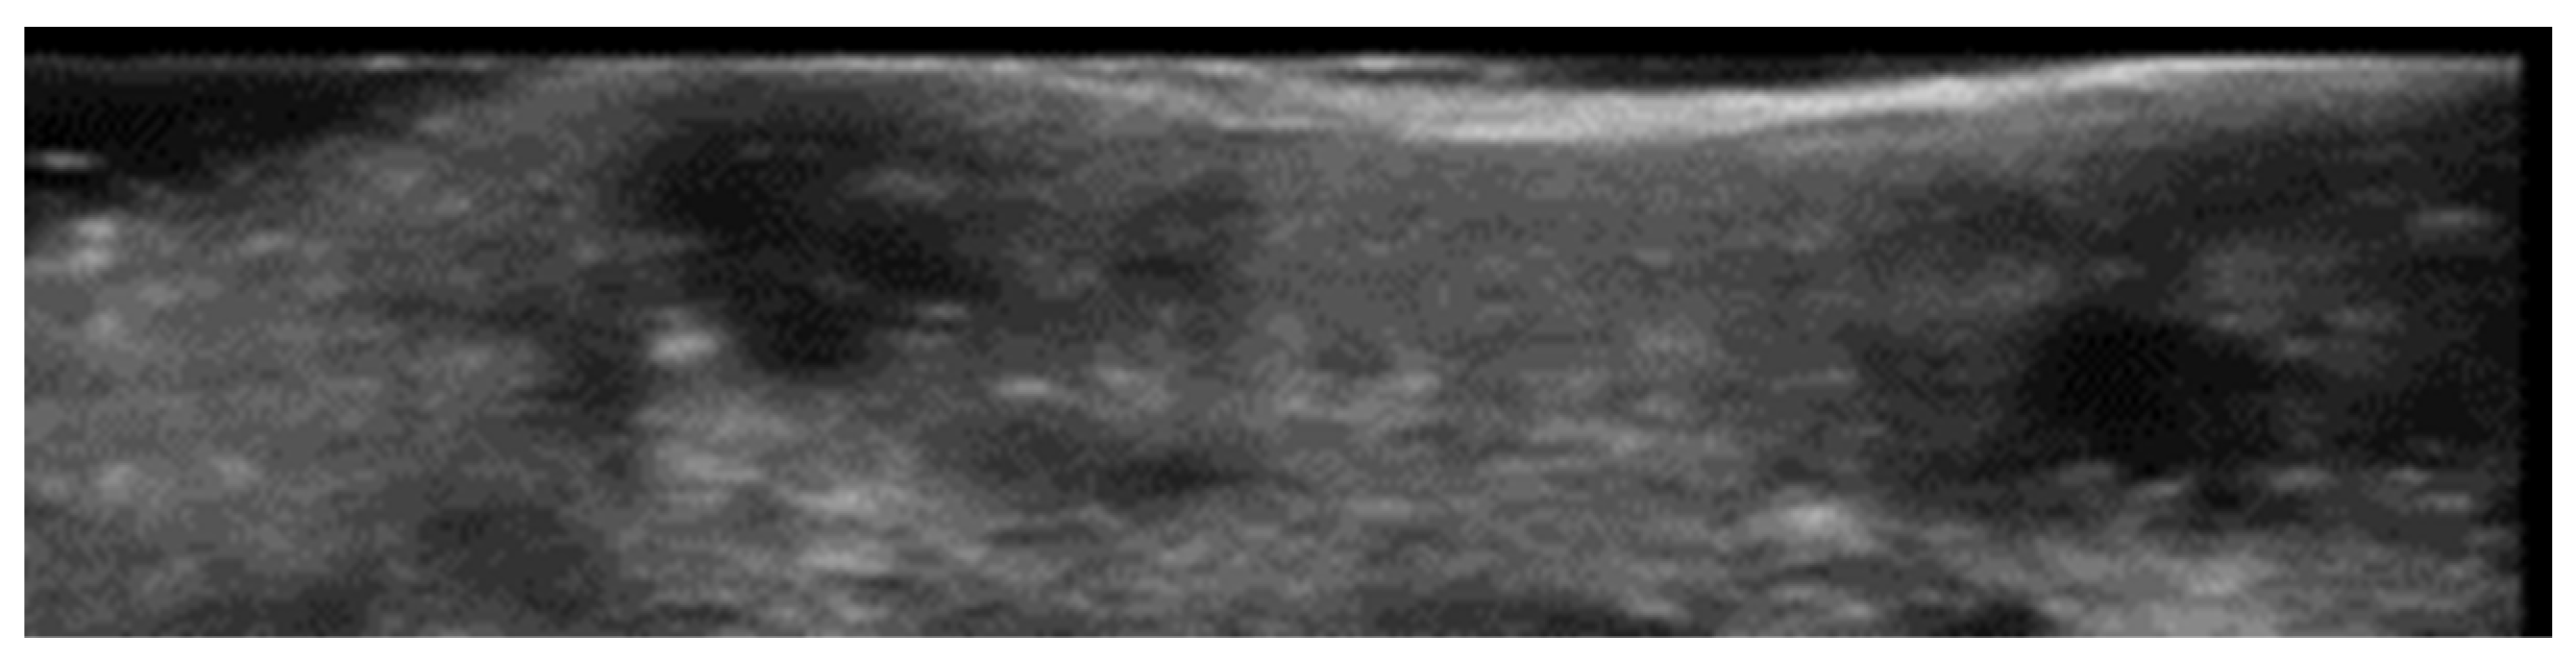

- Salvia, G.; Zerbinati, N.; Manzo Margiotta, F.; Michelucci, A.; Granieri, G.; Fidanzi, C.; Morganti, R.; Romanelli, M.; Dini, V. Ultra-High-Frequency Ultrasound as an Innovative Imaging Evaluation of Hyaluronic Acid Filler in Nasolabial Folds. Diagnostics 2023, 13, 2761. [Google Scholar] [CrossRef]

- Cavallieri, F.A.; Balassiano, L.K.A.; Munhoz, G.; Tembra, M.F.; Wortsman, X. Ultrasound in Aesthetics: Filler and Non-Filler Applications. Semin. Ultrasound CT MRI 2024, 45, 251–263. [Google Scholar] [CrossRef] [PubMed]

- Qiao, J.; Jia, Q.N.; Jin, H.Z.; Li, F.; He, C.X.; Yang, J.; Zuo, Y.G.; Fu, L.Q. Long-Term Follow-Up of Longevity and Diffusion Pattern of Hyaluronic Acid in Nasolabial Fold Correction through High-Frequency Ultrasound. Plast. Reconstr. Surg. 2019, 144, 189e–196e. [Google Scholar] [CrossRef] [PubMed]

- Jiang, L.; Yuan, L.; Li, Z.; Su, X.; Hu, J.; Chai, H. High-Frequency Ultrasound of Facial Filler Materials in the Nasolabial Groove. Aesthetic Plast. Surg. 2022, 46, 2972–2978. [Google Scholar] [CrossRef]

- Chai, H.; Su, X.; Yuan, L.; Li, Z.; Jiang, L.; Liu, Y.; Dou, M.; Hu, J. High-Frequency Ultrasound Imaging Findings of Different Mental Injectable Soft Tissue Fillers. Aesthetic Plast. Surg. 2022, 46, 2995–3002. [Google Scholar] [CrossRef]